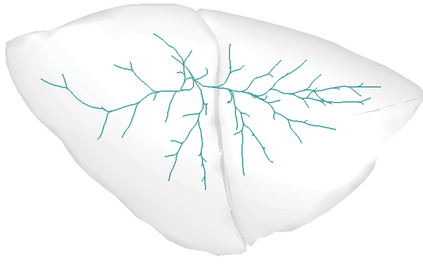

Recent advances in imaging techniques have enabled us to visualize lung tumors or nodules in early-stage cancer. However, the positions of nodules can change because of intraoperative lung deflation, and the modeling of pneumothorax-associated deformation remains a challenging issue for intraoperative tumor localization. In this study, we introduce spatial and geometric analysis methods for inflated/deflated lungs and discuss heterogeneity in pneumothorax-associated deformation. Contrast-enhanced CT images simulating intraoperative conditions were acquired from live Beagle dogs. Deformable mesh registration techniques were designed to map the surface and subsurface tissues of lung lobes. The developed framework addressed local mismatches of bronchial tree structures and achieved stable registration with a Hausdorff distance of less than 1 mm and a target registration error of less than 5 mm. Our results show that the strain of lung parenchyma was 35% higher than that of bronchi, and that subsurface deformation in the deflated lung is heterogeneous.